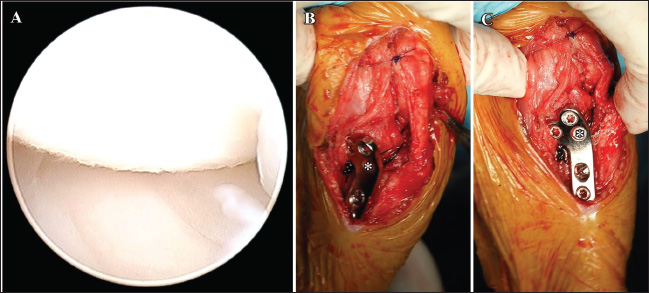

During the tibial compression test post-TPLO plate placement, tibial cranial subluxation and internal rotation occurred intraoperatively. An LFTS was placed using a No. 3 monofilament nylon and an LFTS needle (BEAR Medic Co., Japan) as follows: a single strand of LFTS was passed around the lateral femoral fabella, cut at the needle, and both ends passed under the patellar ligament. One end of the strand was then passed proximally to the cranial screw under the TPLO plate, and the other end was passed distally through the same screw (Fig. 3A). The surgeon’s knot was ligated to the caudal side of the TPLO plate (Fig. 3B). The resolution of the tibial dislocation was confirmed with a second tibial compression test. The incision was closed in three layers, and two orthogonal postoperative radiographs were acquired to evaluate the position of the implants and bone fragments. A modified Robert Jones bandage (soft padded bandage) was applied under general anesthesia after postoperative radiography (Fig. 1B and E) and maintained for 2 days. The non-steroidal anti-inflammatory agent firocoxib (Previcox®; Boehringer Ingelheim Animal Health Japan Co., Ltd., Japan) was administered orally at 5 mg/kg every 24 hours, and cefazolin (Cefaclear®; Kyoritsu Seiyaku Co., Japan K.K., Japan) at 20 mg/kg every 12 hours for 5 days postoperatively. Lameness evaluation, client satisfaction, and radiographic follow-up were performed at 10 days and 4, 8, and 14 weeks postoperatively.

Fig. 3. LFTS following the TPLO plate placement in the right hind limbs. The nylon suture is passed around the lateral femoral fabella. Both ends of the suture are passed under the patella ligament subsequently. One end of the suture is passed proximally, and the other end of the suture is passed distally to the cranial screw (asterisk) under the TPLO plate (A and B). The surgeon’s knot is ligated on the caudal side of the TPLO plate (arrow, B).

Arthroscopy and surgery were performed under general anesthesia. Arthroscopy revealed complete CCLR and medium-stage angiogenesis of the caudal cruciate ligament with no damage to the medial meniscus observed (Fig. 6A). A No. 11 blade was used to remove the remaining portion of the cranial cruciate ligament. TPLO of the left limb was performed as described previously. LFTS was placed in the same manner as described previously owing to tibial cranial subluxation and internal rotation intraoperatively post-TPLO (Fig. 6B and C). Subluxation or rotation was not observed following the second tibial compression test. The medications administered post-surgery of the right limb were also prescribed based on postoperative radiographs (Fig. 4B and E).

Fig. 6. Arthroscopic image of the medial meniscus and LFTS following the TPLO plate placement on the left limb. The medial meniscus is intact (A). The nylon suture is passed around the lateral femoral fabella. Both ends of the suture are passed under the patella ligament. One end of the suture is passed proximally, and the other end of the suture is passed distally to the cranial screw (asterisk) under the TPLO plate (B and C). The surgeon’s knot is ligated on the caudal side of the TPLO plate (arrow, C). F=femur; M=medial meniscus; T=tibia.